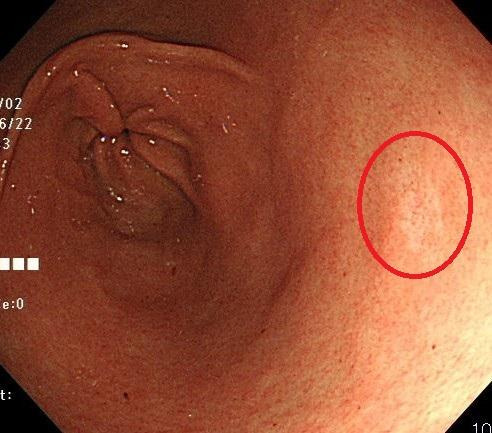

위내시경 조직검사 하는 이유에서 가장 중요한 이유는 위암이나 선종 같은 종양성 병변의 확진입니다. 내시경에서 붉게 변하거나, 혹처럼 솟은 부위, 궤양이 깊게 패인 부위가 보일 때 암이 의심되지만, 실제 암인지 염증인지 구분은 어렵습니다. 위 조직검사 하는 이유는 이 구분을 확실하게 해 주기 때문입니다. 병리과에서는 세포의 핵 모양, 세포 배열, 분화 정도 등을 관찰하여 ‘조기위암’, ‘선종’, ‘이형성’ 등으로 판별합니다. 이를 통해 내시경 절제술로 끝낼 수 있을지, 수술이 필요한지를 결정할 수 있습니다.

5. 용종(폴립)의 성격 구분

용종은 대부분 양성이지만, 일부는 선종이나 조기암일 수 있습니다. 특히 크기가 1cm 이상이거나 표면이 거칠고 붉은 경우는 선종 가능성이 높습니다. 이때 조직검사로 성격을 파악한 뒤 절제술 여부를 결정합니다.